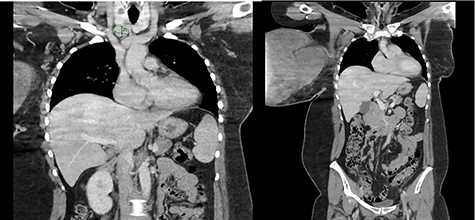

The wound swab showed heavy growth of Staphylococcus aureus susceptible to Flucloxacillin. On ultrasonography, the right breast was completely replaced by a massive solid, heterogenous mass. It demonstrated internal vascularity and numerous cleft cystic spaces and leaf-like internal architect. Mammogram was not feasible due to the incompressible nature of the right breast, patient discomfort and the size of the lesion. A chest computed tomography was ordered for staging/metastatic workup and preoperative planning. Multiple enlarged right axillary lymph nodes measuring up to 12 mm and a 19 mm lymph node in the right supraclavicular region were noted with no distant metastasis (Fig. 2). The core biopsy showed features of spindle cell lesion with the differentials being borderline PT versus metaplastic carcinoma.

Enlarged supraclavicular lymph node and partially imaged massive tumour in the right breast.